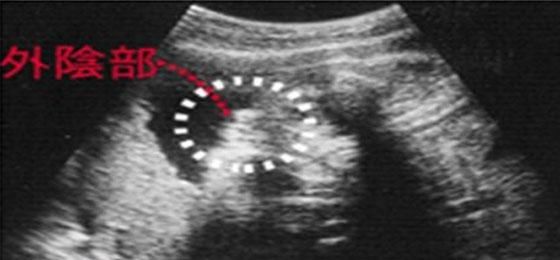

四维单子上有男女暗示 男胎儿小鸡b超显示图像

众所皆知,B超看胎儿性别是最科学,也是最准确的方法。尽管大家都知道如今国家有明文四维彩超怎么看性别?

女性妊娠24周后通过做四维彩超一般就可看出男女,看性别与胎儿的体位有关系,但如果胎儿双腿紧闭就无法判断

如何通过四维彩超单看胎儿性别 1、看四维彩超单上的字母看男女 在彩超单上,顶头最右边有两行字,是英文